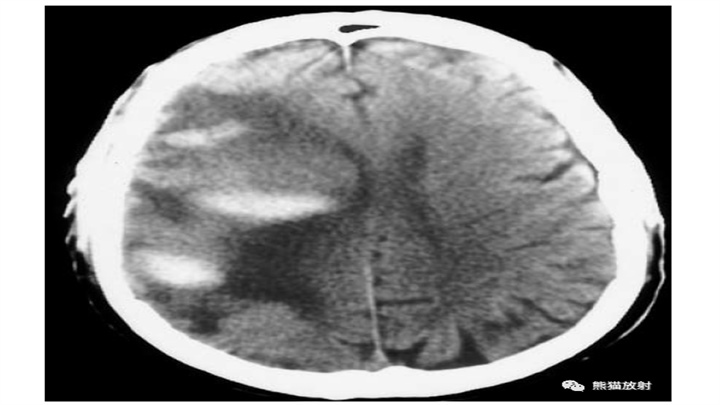

慢性酒精中毒患者,大量脑实质出血,脑内不规则的高密度灶,和周围脑白质内广泛液化表现交替出现。伴随脑萎缩,病变有一定占位效应。